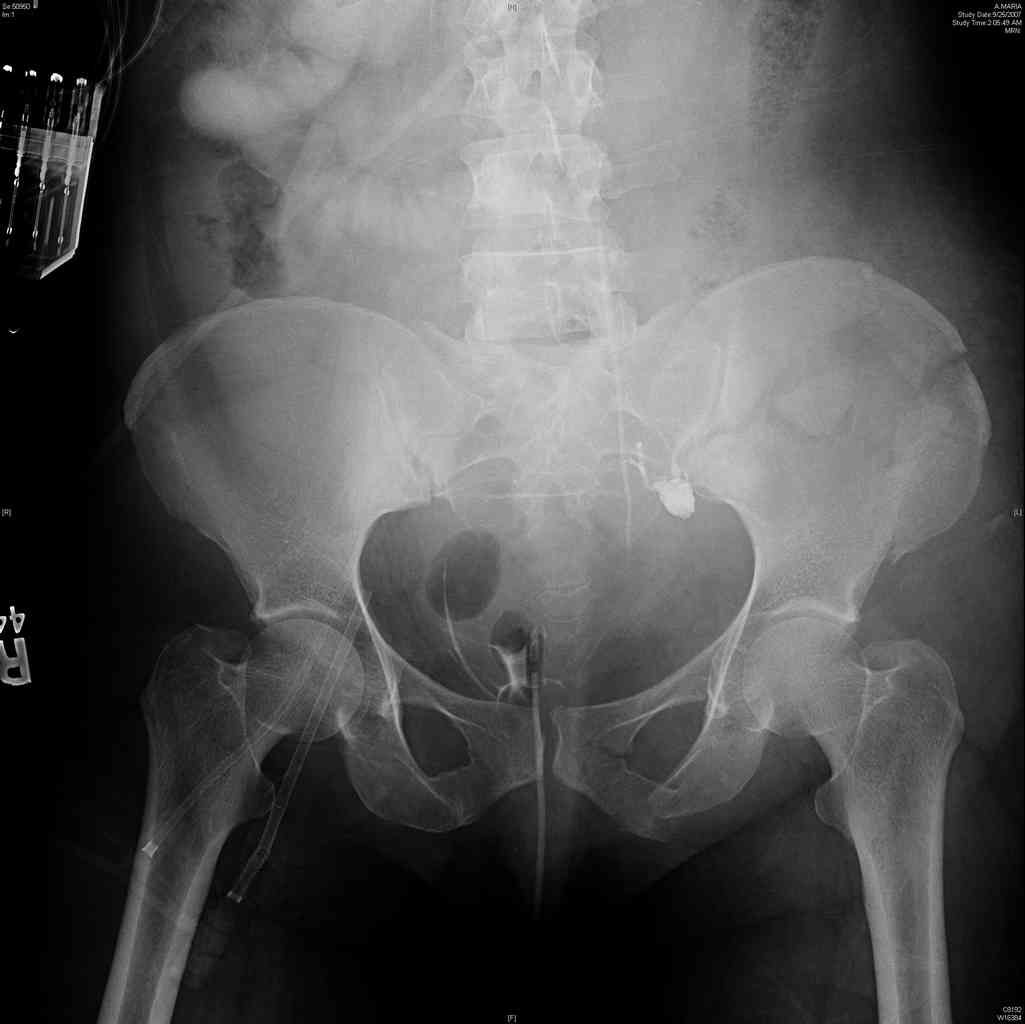

comminuted crescent fx

40 ish female ejected from car. Unstable, DPL negative, went to angio and had her pelvic bleeds embolized after many units of blood. GCS 6, floating elbow, clavicle, bothbones, etc.

My standard approach to this pelvis would be posterior, reduce/lag/plate thecrest, reduce/plate the caudal extent on the posterior crest and 1-2 lags back to front. In this case, the crest comminution seems to make plating all the way to the ASIS useless, as the plate would be on free floating fragments. Would plating the posterior extent of the fracture to secure the reduction at the SI joint and 2 screws back to front be sufficient fixation? Would anyone do a perc reduction and perc back to front screws, and would that be sufficient if the SI joint could be reduced (although I don't see how this could be accurately reduced closed). Would an ilioninguinal with a pelvic brim plate and posterior column screws be a better approach, although reducing the SI would be more indirect and less accurate?

It's a comminuted iliac fracture involving the GS notch and all that

implies...use the lateral interval of an ilioinguinal, sequentially reduce,

and fix...if you want to, you can attach the dominant unstable fragment to

both the stable posterior iliac fragment and also to the anterolateral portion of the sacrum using plates...if you choose to anchor to both, the implants get congested on the iliac side of the SI joint so be precise with contouring and such applications...perhaps and based on the images shown, an iliosacral screw would only augment the construct if applied to the second sacral segment (but this is difficult to assess on the images shown). The crest components can be held securely with screws and/or peripheral plating.

Thanks. I probably didn't include enough images on the CT, but it didn't look to me like an SI screw would be of value except into S2, which I am not

comfortable placing. I will post finals if the neurosurgeons let me operate on her. ICPs still a problem.